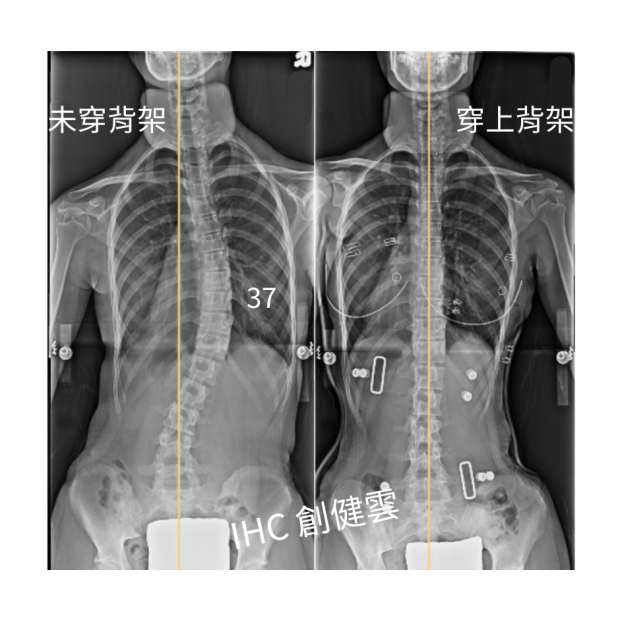

13歲脊椎側彎女孩,胸腰彎37度